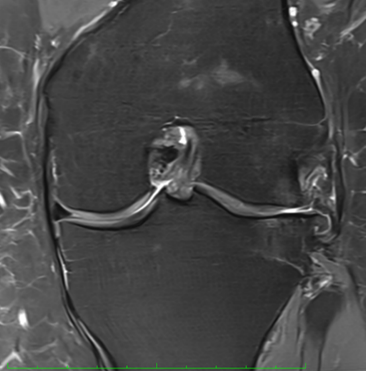

MRI scans illustrating the improvements regarding Group 2 are presented below, showing pre-treatment images with evident cartilage defects, pronounced bone marrow edema, and synovial inflammation, followed by post-treatment scans demonstrating improved joint structure, reduced edema, and decreased inflammation (Figures 12-29).

MRIs of Group 2

Figure 18: Female, 77 years, pre-intervention MRI.

Figure 19: Female of figure 18, two-month follow-up MRI: MSC plus ChondroFiller® liquid.